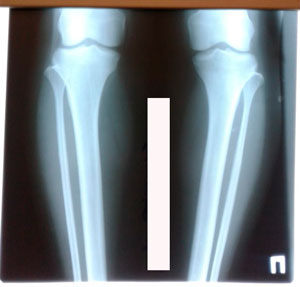

Исходник - 35 лет.

Дата операции - 06.01.2020 г.

на фиксации